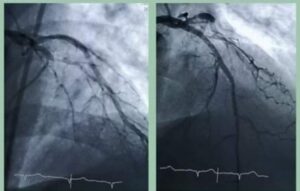

نجح فريق طبي بوحدة القسطرة القلبية بمستشفيات قنا الجامعية، في علاج انسداد تام بالشريان التاجي الأيسر النازل باستخدام القسطرة العلاجية وتركيب دعامة دوائية بنجاح في إطار المبادرة الرئاسية للقضاء على قوائم الانتظار، حيث كان المريض يعاني من أزمات قلبية متكررة وتعتبر تلك التقنية حل بديل لجراحة القلب المفتوح وزراعة الشرايين، وذلك تحت رعاية الدكتور يوسف غرباوي رئيس الجامعة، وإشراف الدكتور علي عبدالرحمن غويل عميد كلية الطب بقنا، والدكتور محمد يوسف المدير التنفيذي للمستشفيات الجامعية.

ضم الفريق الطبي الدكتور أريج الخطيب مدرس أمراض القلب بطب قنا والدكتور محمد عبد الله مدرس أمراض القلب بطب قنا والدكتور أحمد جابر مدرس أمراض القلب بطب قنا والطبيب مصطفى علي مدرس مساعد أمراض القلب بطب قنا باشراف أ.م.د/ حسام إسماعيل رئيس وحدة قسطرة القلب بمستشفيات قنا الجامعية.